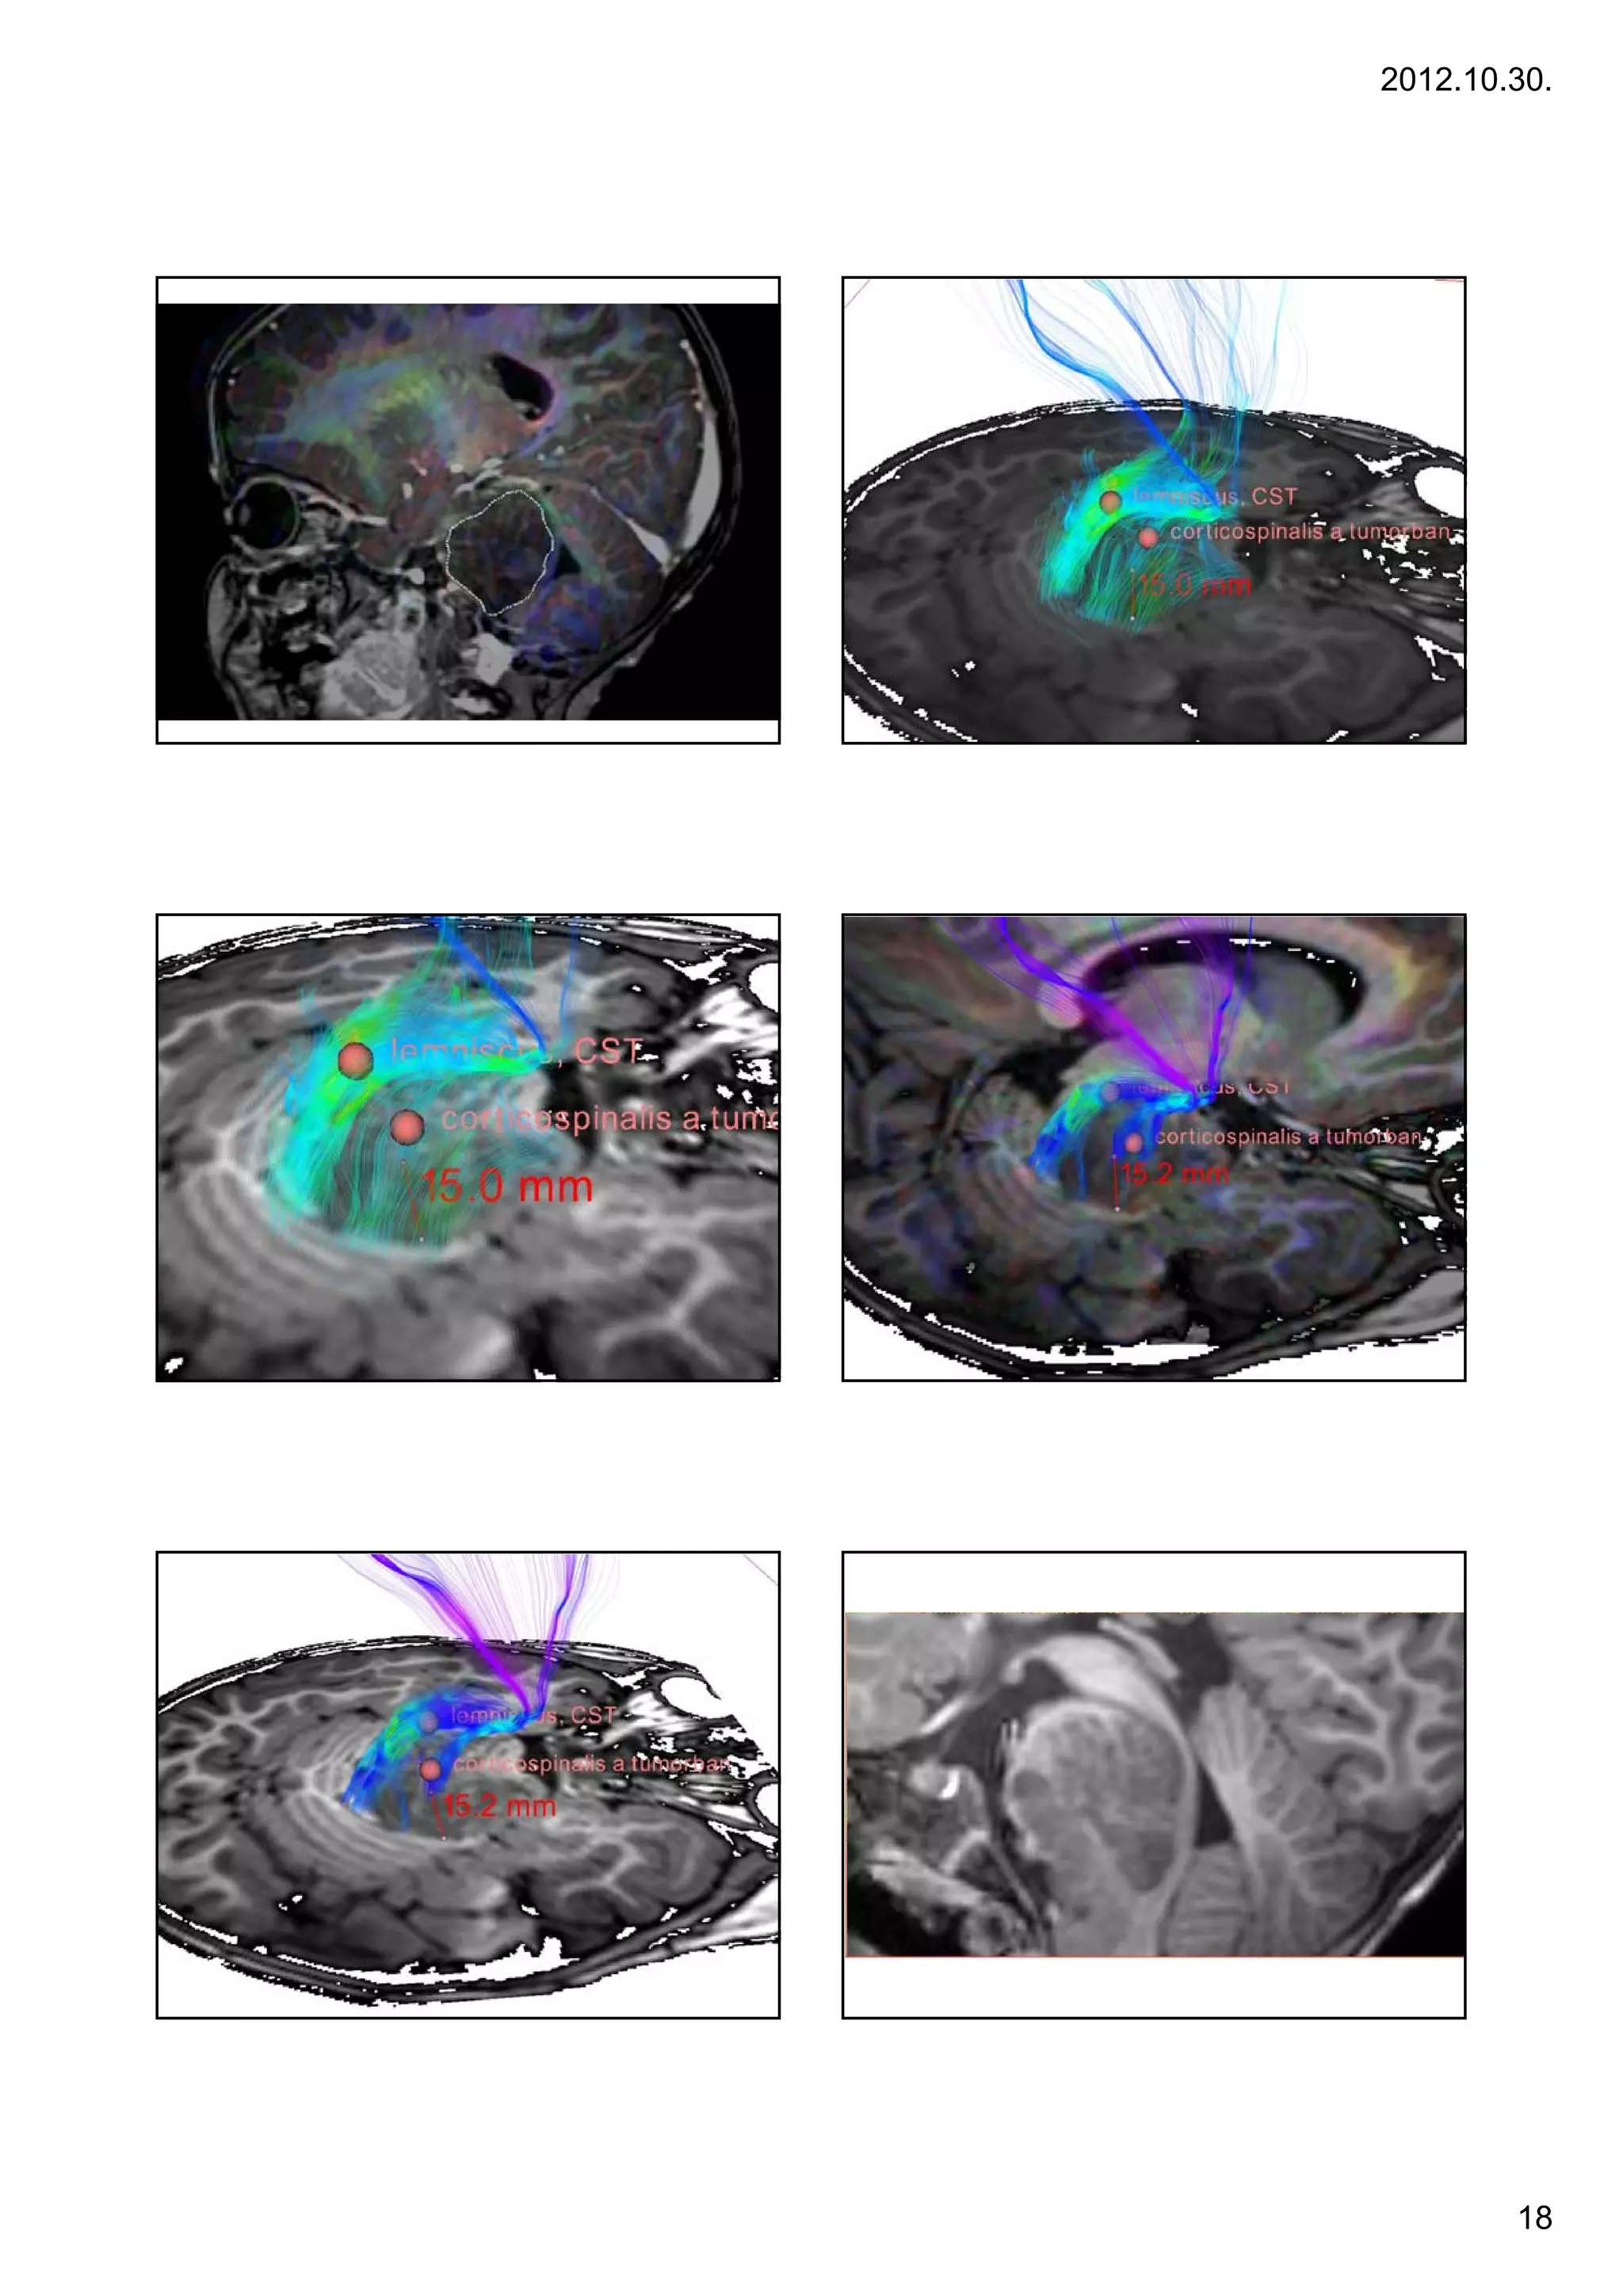

Diffusion information:                                                 Diffusion information:

17           DTI and fibertracking                                        18        DTI and fibertracking

• Segmenting and localizing main structures of the WM (pl. tr. cortico-

spinalis, FLS, cc)